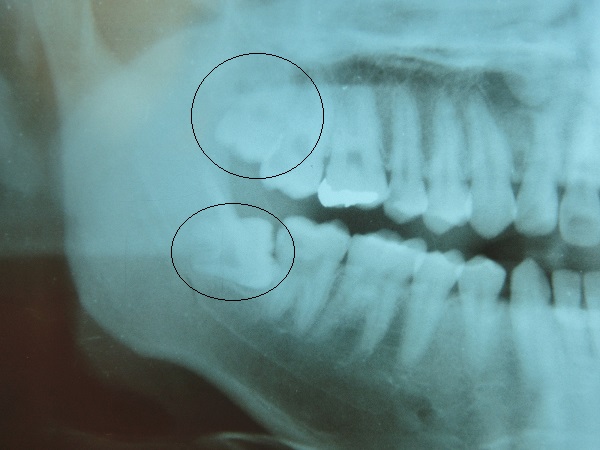

また、あらかじめレントゲンで根の位置や、歯の生えてる向きや長さなど、しっかり確認してから抜歯します。

CASE1

右上のケースは時間にして、1分くらいで抜歯します。

右下のケースは15分程度かかります。